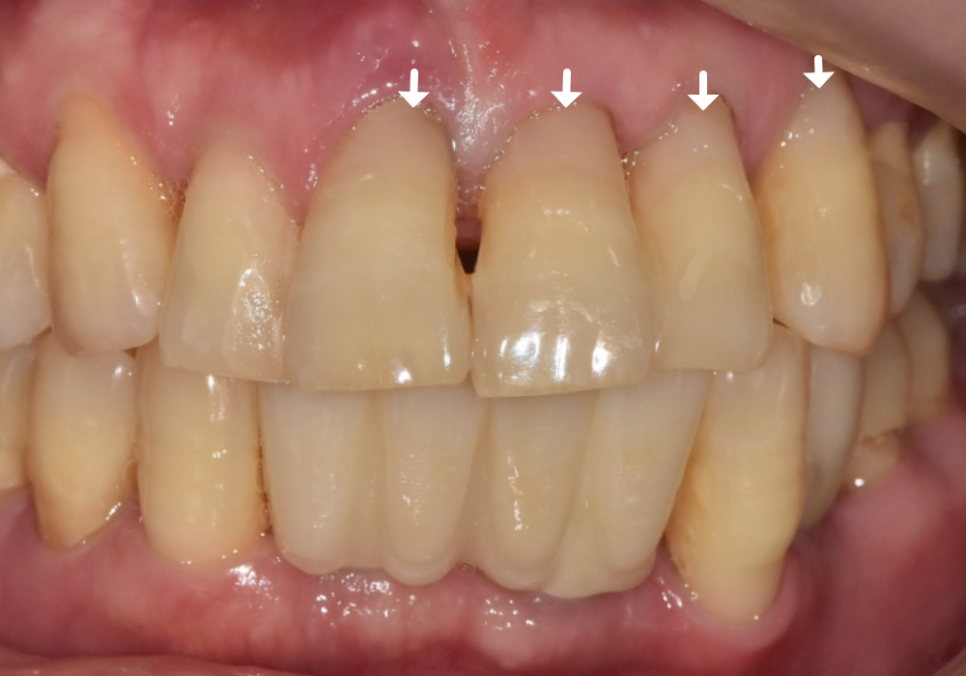

환자분께서는 앞니 부위라

심미적인 부분도 중요하게 생각하셨기에

치아색에 맞는 레진으로

꼼꼼하게 메워드리는 치료를 진행했습니다.

250417

잇몸 라인과 치아 색상을 자연스럽게 맞춰드려

심미적으로 아주 만족스러운 결과가 나왔네요.^^

241224 (전) 250417(후)